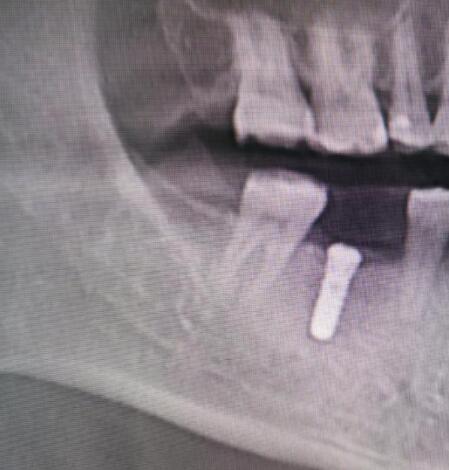

术后复查

在手术中,特别采用CPF离心机制成的纤维蛋白凝块,不仅具有更高的抗张强度更好的粘性,且由患者自体静脉血制成,无排异反应不添加任何外来物质,避免交叉感染;具有生物活性,富含多种生长因子,可促进软硬组织再生,加速创口愈合止血抗感染能力,有效应对术后并发症。具体病情情况请到玉溪市人民医院口腔颌面整形外科门诊进行就诊咨询。